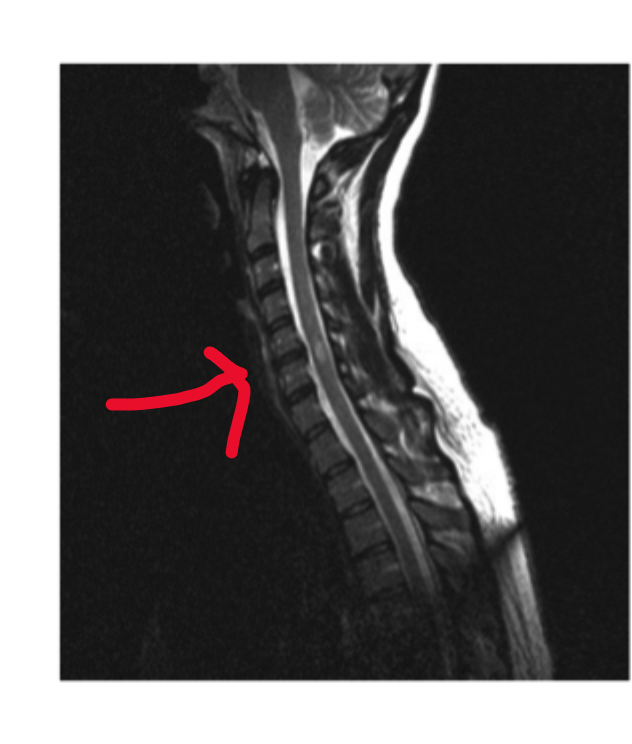

Q

Vilken nivå sitter tumören vid?

A

Intermedullär tumör C5-C6